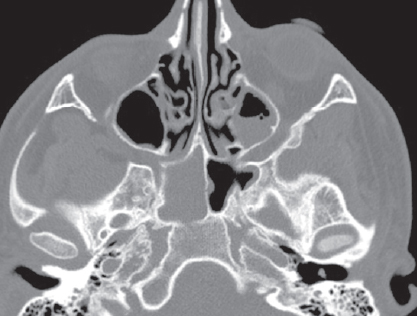

По результатам МСКТ ОНП от 16.06.2021: КТ-признаки синусита, осложненного эмпиемой левой лобной доли (рис. 3). В сравнении с данными МСКТ от 04.06.2021 отмечается положительная динамика в виде улучшения пневматизации левой лобной и верхнечелюстной пазух, а также клеток решетчатого лабиринта.

Рис. 3. Мультиспиральная компьютерная томография околоносовых пазух и головного мозга от 16.06.2021: а — аксиальная проекция в режиме brain. Отмечается увеличение пневматизации лобной пазухи; b — коронарная проекция в режиме brain. Восстановлена пневматизация клеток решетчатого лабиринта слева, сохраняется очаг поражения левой лобной доли; c — коронарная проекция в режиме brain. Восстановлена пневматизация левой верхнечелюстной пазухи; d — сагитальная проекция в режиме brain. Улучшение пневматизации левой лобной пазухи; e — аксиальная проекция в режиме skull. Улучшение пневматизации левой лобной пазухи; f — коронарная проекция в режиме skull. Восстановлена пневматизация левой верхнечелюстной пазухи; g — коронарная проекция в режиме skull. Восстановлена пневматизация левой верхнечелюстной пазухи, пристеночный отек; h — сагиттальная проекция в режиме skull. Улучшение пневматизации клеток решетчатого лабиринта, лобной пазухи

Fig. 3. Multispiral computed tomography of the paranasal sinuses and brain from 06.16.2021: a – axial projection in brain mode. There is an increase in pneumatization of the frontal sinus; b – coronary projection in brain mode. The pneumatization of the cells of the ethmoid labyrinth on the left was restored, the lesion of the left frontal lobe remains; c – coronary projection in brain mode. Restored pneumatization of the left maxillary sinus; d – sagittal projection in brain mode. Improvement of pneumatization of the left frontal sinus; e – axial projection in skull mode. Improvement of pneumatization of the left frontal sinus; f – coronal projection in skull mode. Restored pneumatization of the left maxillary sinus; g – coronal projection in skull mode. Restored pneumatization of the left maxillary sinus, parietal edema; h – sagittal projection in skull mode. Improvement of pneumatization of cells of the ethmoid labyrinth, frontal sinus